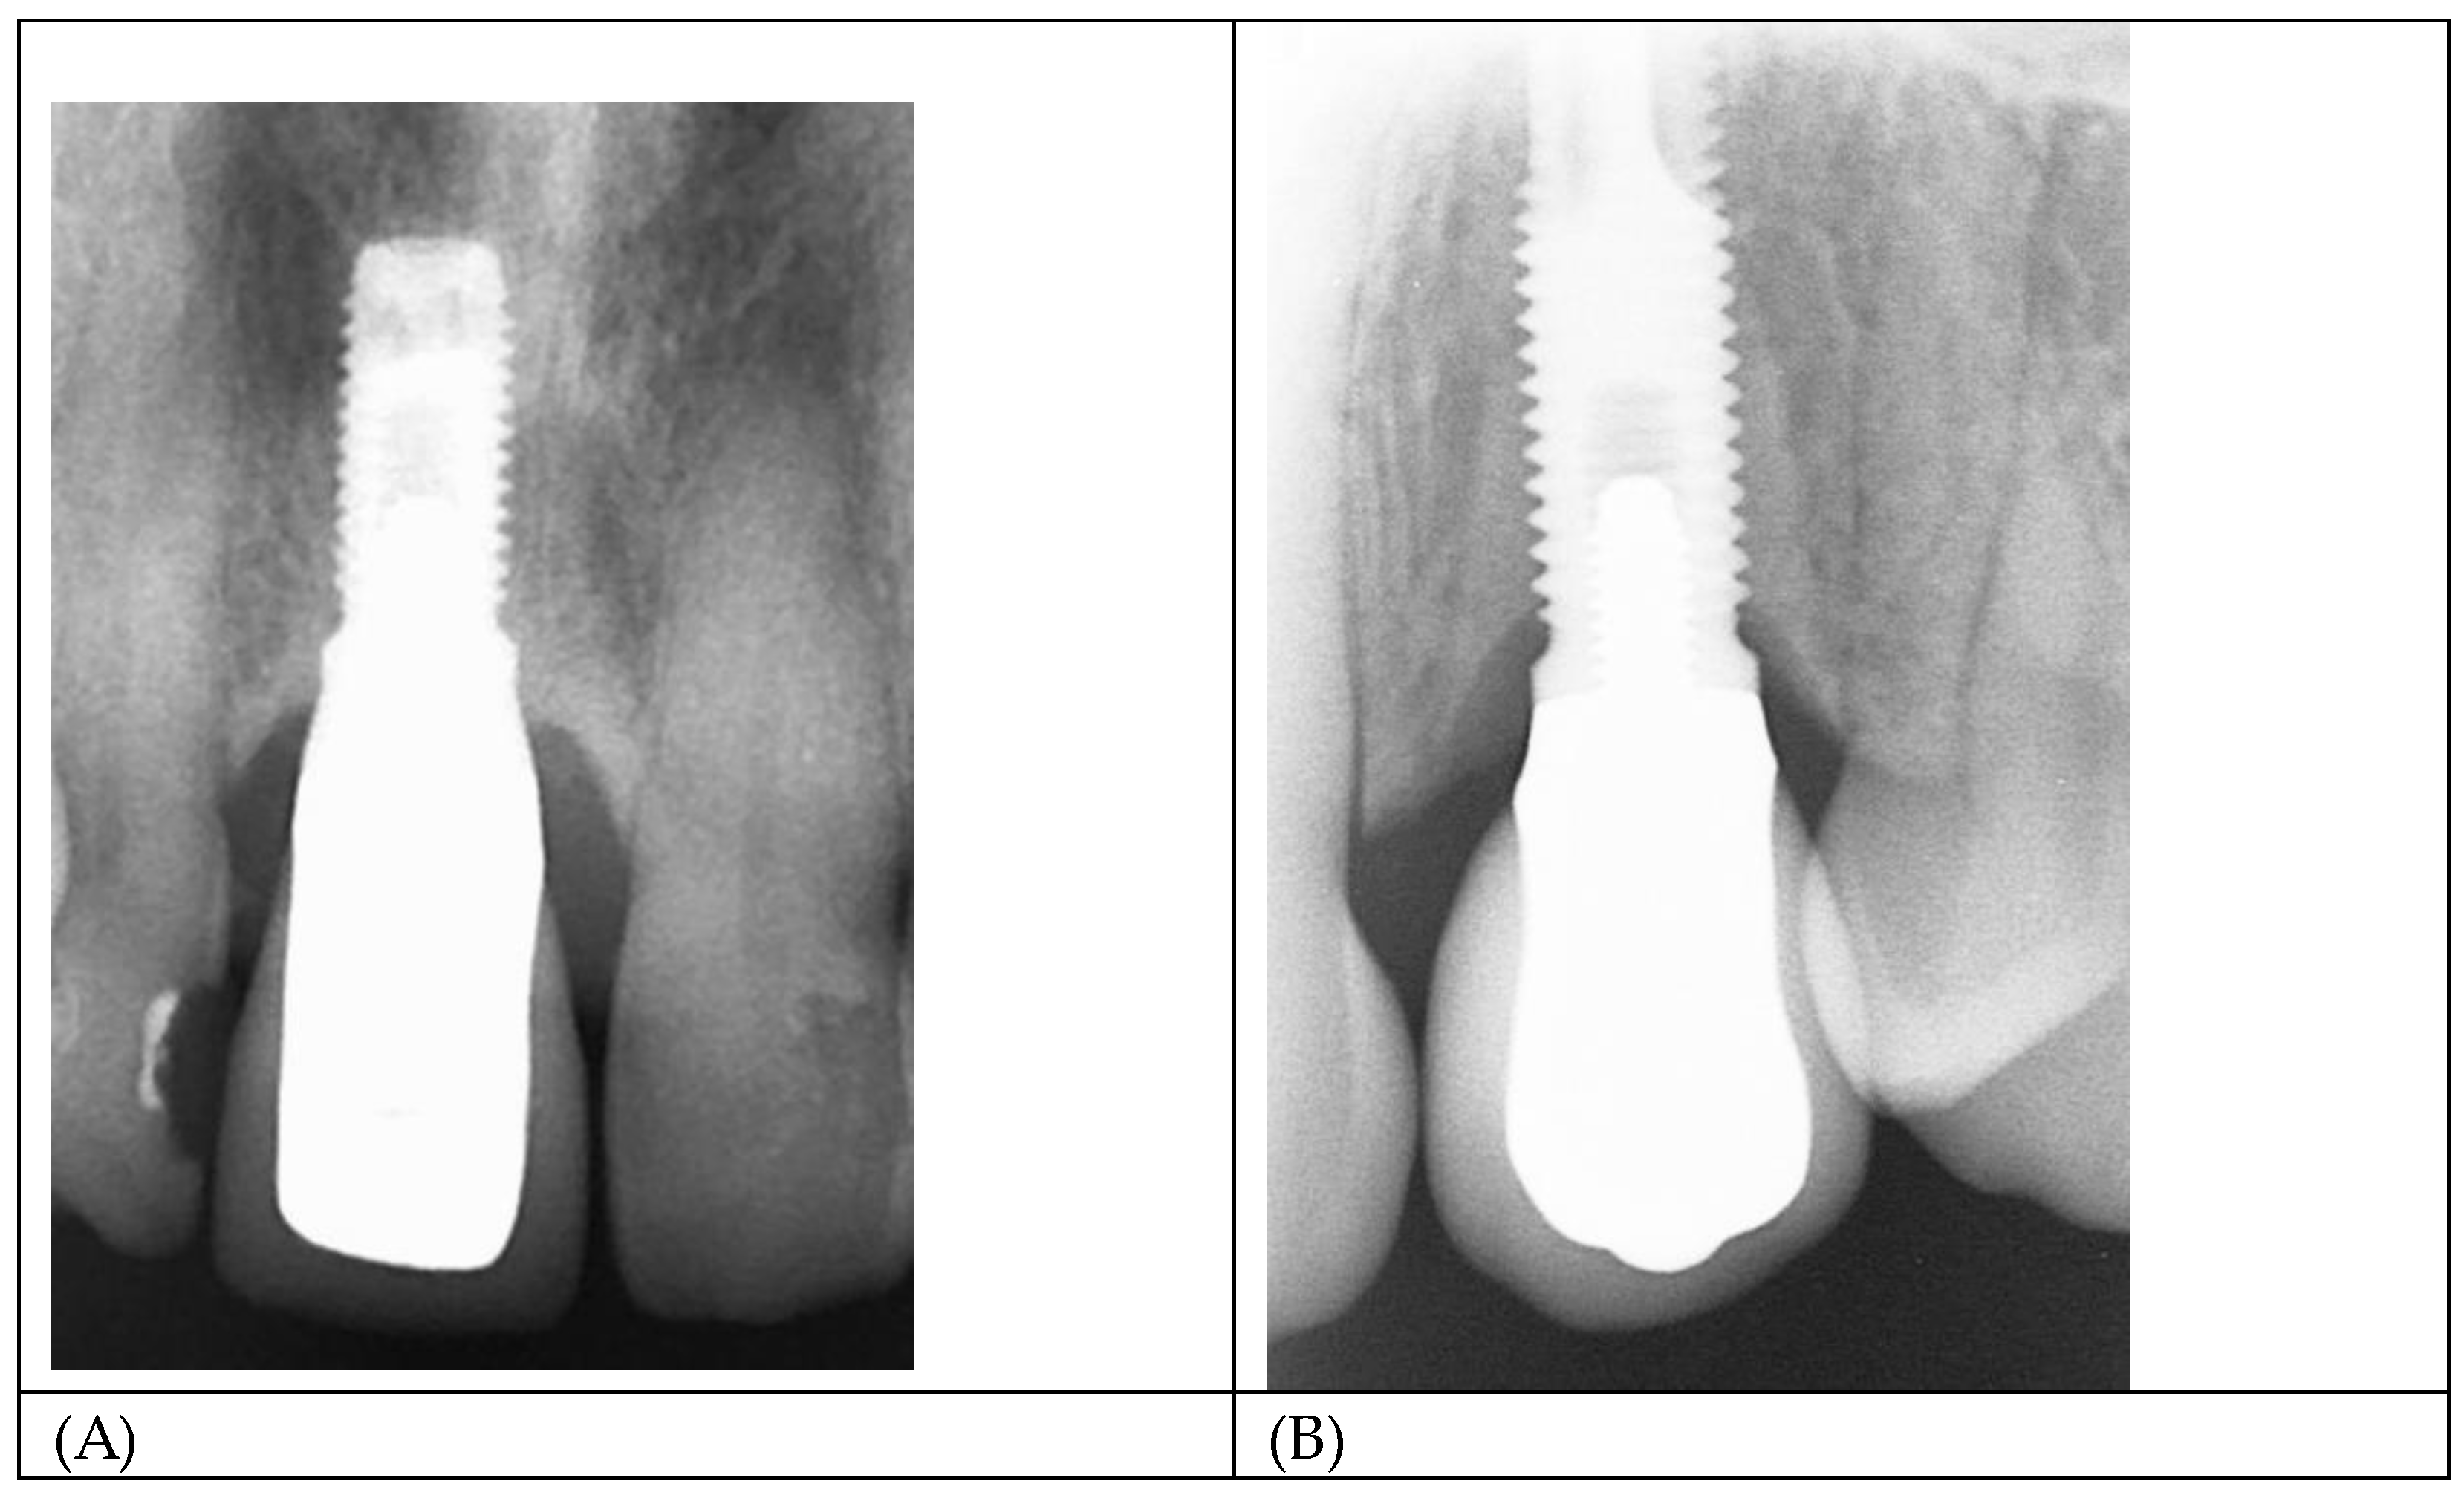

The results of this study may explain the excellent long-term clinical outcomes of a previously published study where castable, gold-plated abutments were used.[17] Figure 11 A and B show radiographs of two single implant crowns in-situ for 21years. It could be assumed that the screw seat and/or the implant/abutment interface in A have formed an effective seal against bacterial leakage through the micro-gap but not in B, possibly contributing to marginal bone loss to the first thread.

Figure 11. (A,B) Radiograph of single implant crowns, in-situ for 21 years. In A, there is no radiolucency at the implant/abutment interface, indicative of an effective seal at either the screw/thread or implant/abutment connections. In B the radiolucency extending to the first thread is indicative of a zone of inflammation resulting in loss of MBL and possibly associated with bacterial leakage through the micro-gap.